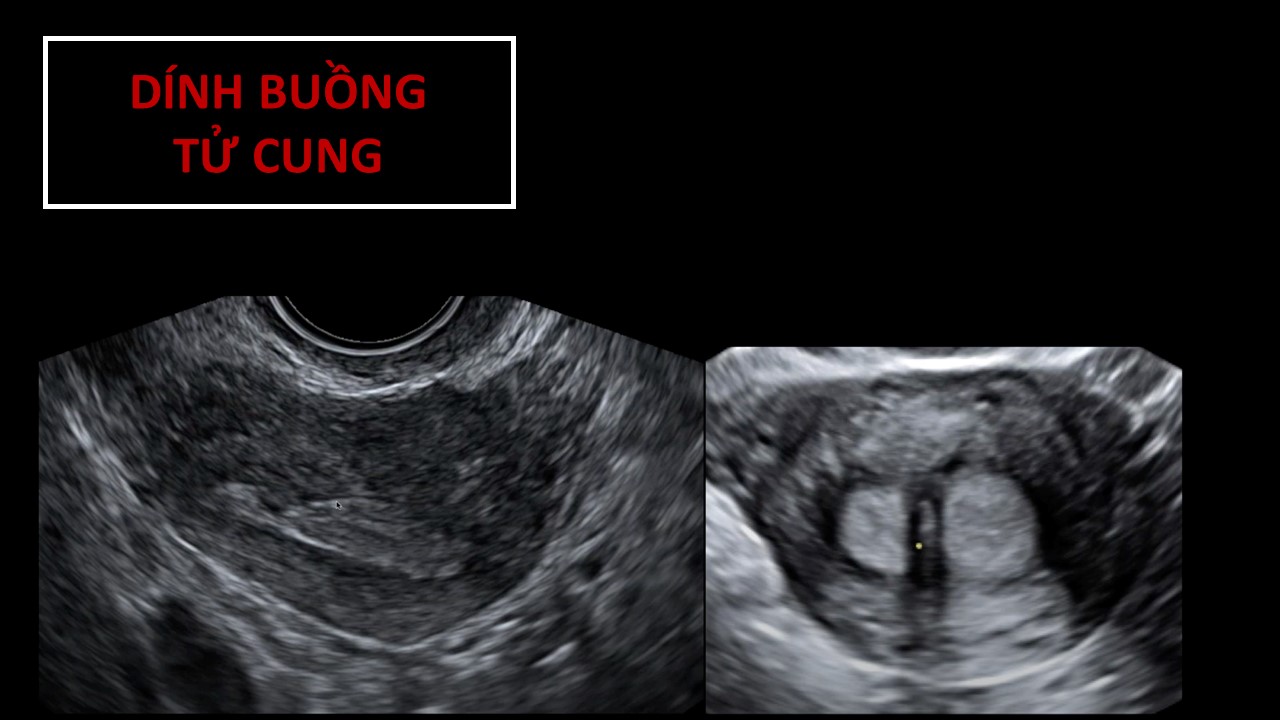

Vai trò của siêu âm trong chẩn đoán và điều trị hiếm muộn